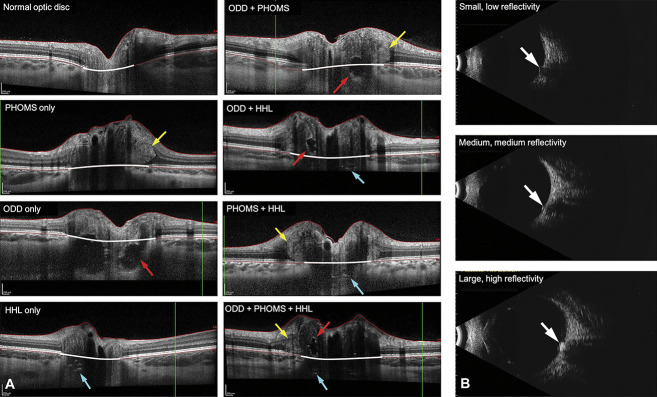

Methods: Pediatric patients referred by a neuro-ophthalmologist to the diagnostic ultrasound clinic for optic nerve head elevation between March 2019 and May 2021 were eligible. Subjects who underwent BSUS and EDI-OCT and were diagnosed with pseudopapilledema based on examination, imaging findings, stability on follow-up, and, in some cases, normal CSF opening pressure were included. ODD were identified on EDI-OCT as structures above the lamina cribrosa with a hyporeflective core and hyperreflective margin prominent superiorly. Hyperreflective horizontal lines (HHL) above the lamina cribrosa without ODD were identified. PHOMS were defined as ovoid, hyperreflective structures above Bruch's membrane external to the optic disc, with similar reflectivity to the retinal nerve fiber layer on OCT and upward deflection of other retinal layers. The BSUSs were read by a separate, masked evaluator who graded the size and reflectivity.

Results: Two hundred thirty-nine eyes (120 patients; 58.3% female; mean age = 11.6 years) with pseudopapilledema were included. EDI-OCT mostly demonstrated PHOMS only (58.1%), followed by PHOMS and HHL (12.6%), and then PHOMS and ODD (11.7%). A combination of PHOMS, ODD, and HHL was found in 8.8%, 1.7% had HHL only, 0.8% had ODD and HHL, and 0.4% had ODD only. 5.9% of eyes were normal on OCT. On BSUS, 78.4% of eyes with only PHOMS demonstrated low or intermediate reflectivity, while 92.9% of eyes with both PHOMS and ODD demonstrated high reflectivity. When HHL was present with or without other findings, a majority demonstrated high reflectivity.

Conclusions: Though PHOMS are hyperreflective on BSUS, ODD are more highly reflective, which may allow clinicians to differentiate between the two if EDI-OCT is unavailable. Eyes with both PHOMS and HHL have similar characteristics to those with ODD, supporting current theories that these lines may be early indicators of evolving drusen.